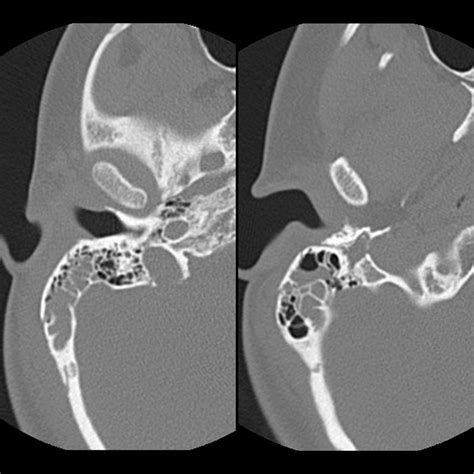

Because the mastoid air cells are deeply embedded within the skull, they cannot be seen through a standard physical ear examination. Instead, doctors rely on advanced imaging techniques to assess their health and structure. These imaging tools are essential for diagnosing conditions like chronic ear infections, mastoiditis, or detecting anatomical abnormalities.

Computed Tomography (CT) Scan The gold standard for visualizing the bony structure and identifying fluid or infection in the air cells.